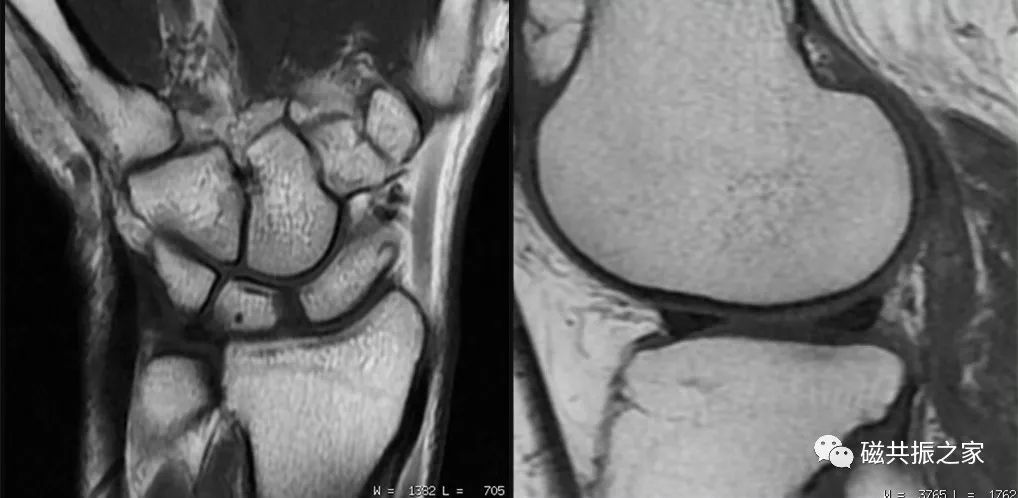

如T1WI较其它序列使用较短的扫描时间即可获得更高的信噪比图像。在四肢关节的扫描中建议T1WI使用较大的矩阵(更小的体素)扫描,以获得更高的图像分辨率。高分辨率的图像不但可以显示更为精细的解剖结构,还能为临床诊疗提供更多的影像学信息。在时间和信噪比都能保证的情况下,对于四肢关节的扫描应尽量采用小的体素扫描,以提高图像的分辨率。

四肢关节的扫描常扫描1-2个方位的T1WI,在实际的临床扫描中建议使用较大的矩阵扫描,以提高图像的分辨率。

同时,在做四肢关节的较高分辨率扫描时,建议采用较弱的压脂程度来保证图像的信噪比。

如上图的压脂程度为80%,下图的压脂为100% 。我们知道MRI的信号主要来自于水和脂肪中的氢质子,虽然较强的压脂程度可突出某些组织间的对比,但更多的脂肪被抑制,图像的SNR会下降,则不利于我们做更高分辨率的图像。在小体素扫描时,使用部分压脂可以保证图像足够的信噪比。